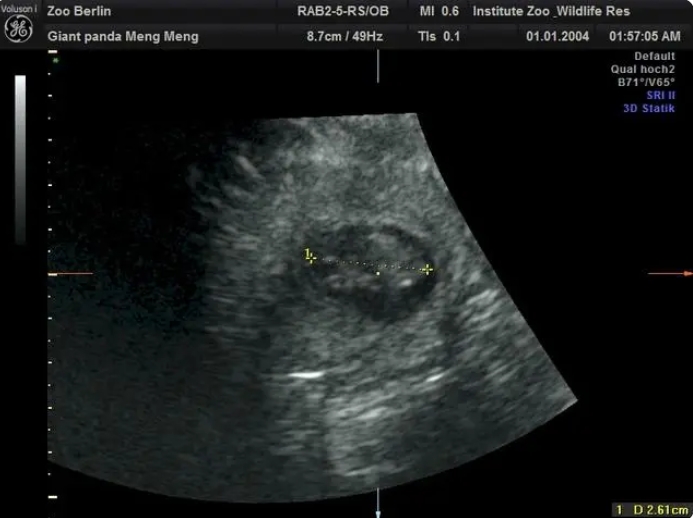

在園方11日上午進(jìn)行的超聲檢查中,工作人員清楚地檢測(cè)到兩個(gè)熊貓?zhí)旱男奶?。目前兩個(gè)胎兒身長約2.5厘米。

柏林動(dòng)物園介紹,根據(jù)目前胚胎的大小,如果一切順利的話,大熊貓雙胞胎預(yù)計(jì)將於8月底出生。